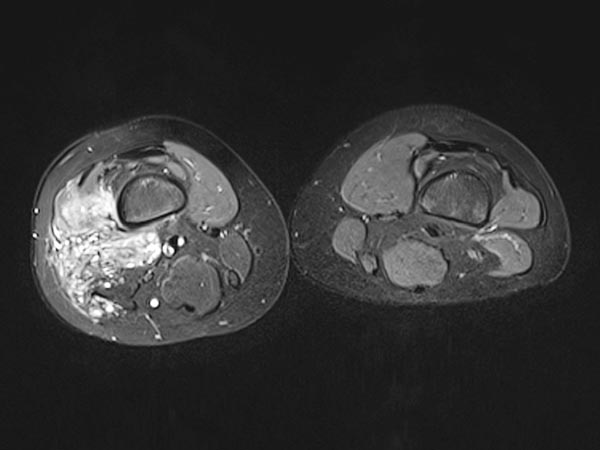

Axial T2-weighted MRI, fat-suppressed, shows the close relationship to the periosteum of the femur. This location is particularly painful due to inflammatory irritation of the periosteum.

T2-weighted MRI without fat suppression in the axial plane reveals inflammatory, fibrotic remodeling of the lesion due to multiple inflammations. The right vastus lateralis of the quadriceps femoris muscle is completely penetrated by the lesion.